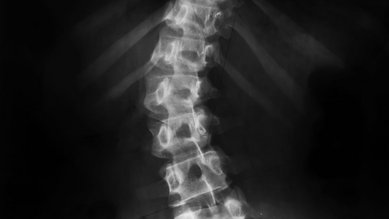

Ergenlikte skolyoz

Ergenlikte skolyoz, omurganın eğrilmesine neden olur. Nedeni bilinmemektedir. Eğrilik devam ederse, düzenli olarak kontrol edilmelidir.